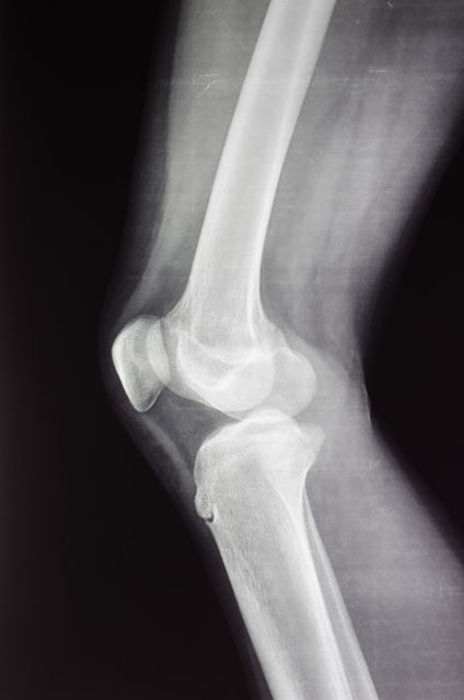

Common Hip and Knee Conditions

Knee Arthritis